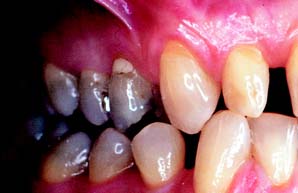

There are significant differences in the adaptive response of patients to occlusal abnormalities. Some individuals are unable to tolerate seemingly trivial occlusal deficiencies, whereas others are able to tolerate distinct malocclusions without obvious symptoms (Fig. 4-22). Most patients seem able to adapt to small occlusal deficiencies without exhibiting acute symptoms.

Fig. 4-22 Patient adaptability: None of the four patients described here expressed any concern about their occlusion. A, Anterior esthetics motivated a 45-year-old woman to seek treatment, although loss of posterior occlusal contact probably contributed to the development of her anterior diastema. B, A 26-year-old woman had no complaints or neuromuscular symptoms, despite contacting only on her second and first molars. C, A patient with amelogenesis imperfecta sought care for esthetic reasons rather than functional complaints. D, A 21-year-old man with congenitally missing lateral incisors had neither functional nor pain complaints when he was referred for fixed prosthodontic care after orthodontic treatment.